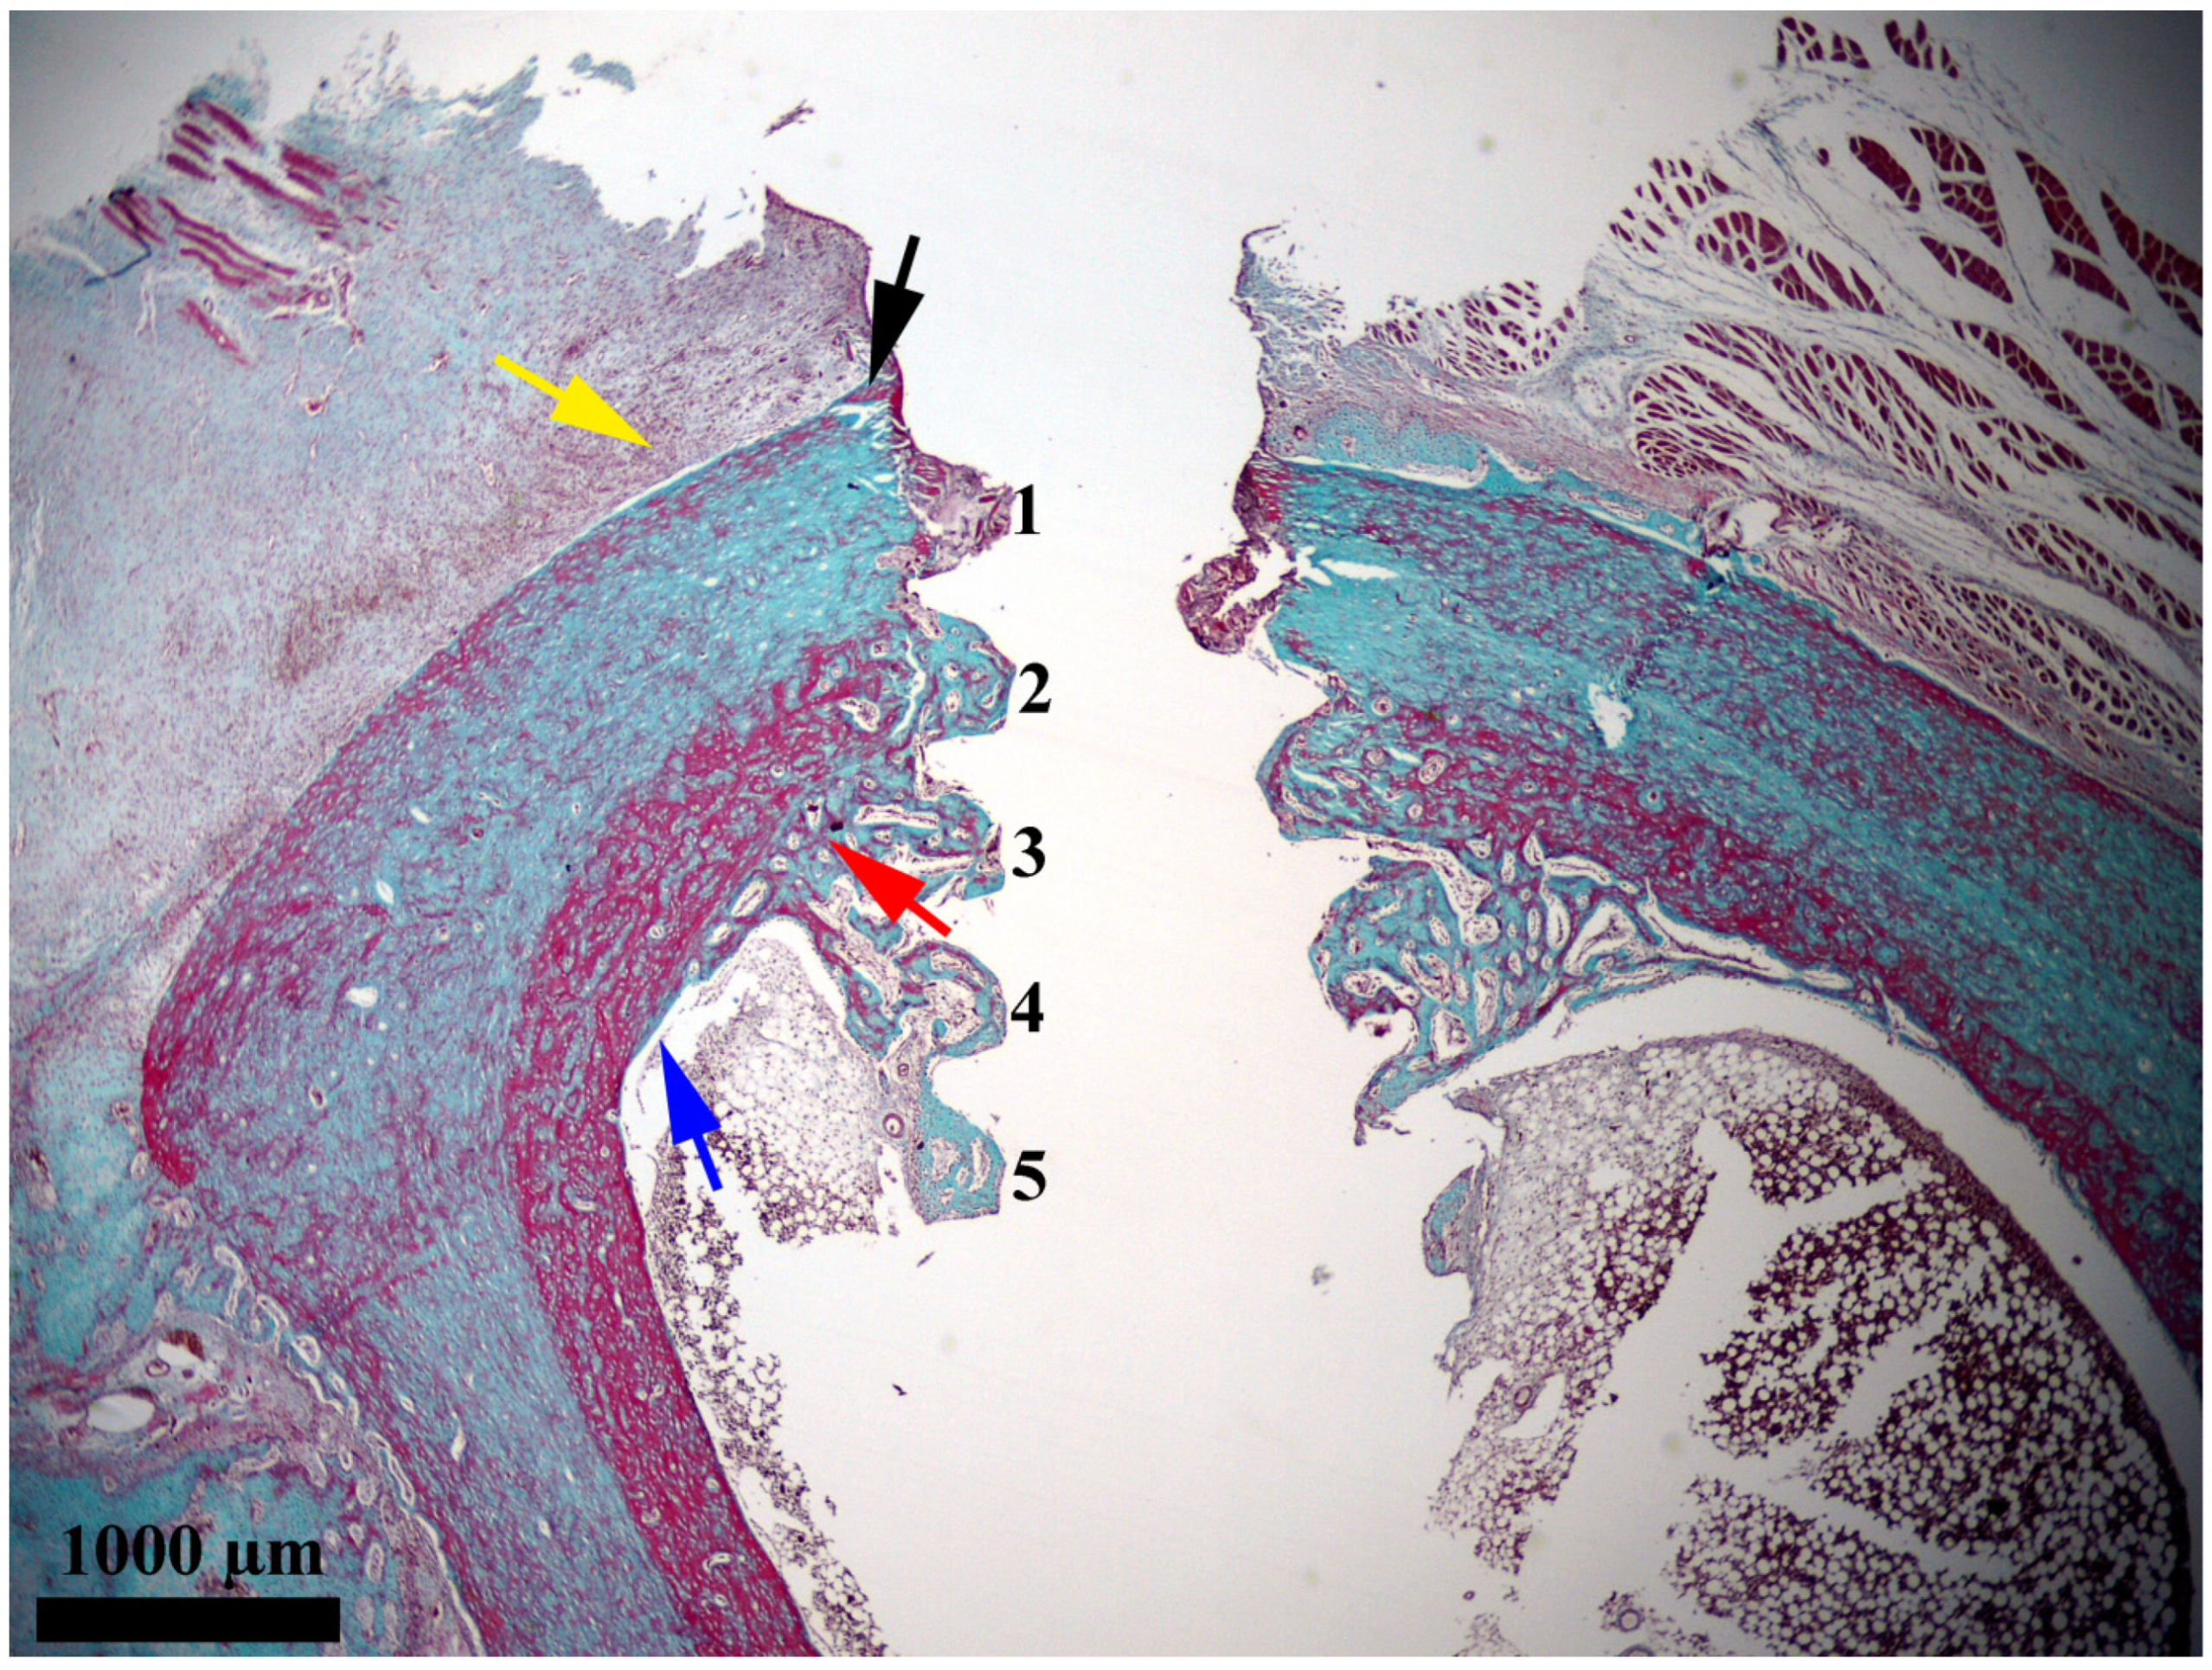

After the insertion of the implants, a rapid evolution of bone proliferation processes at the bone–implant interface was observed at 14 days (Figure 3). At this point in the experiment, the newly proliferated bone was extended over most of the interface. It infiltrated into four of the six grooves between the turns of the implant, namely, grooves 2, 3, 4, and 5. Groove no. 1, which was the closest to the periosteum, was mostly occupied by augmentation material that consisted of bone fragments embedded in fibrin, which dated from the moment when the implants were inserted. Groove no. 6, which was located at the tip of the implant, was not yet filled with newly proliferated bone. Of the four grooves occupied by newly proliferated bone, three of them (i.e., no. 3, 4, and 5) were located in the medullary cavity, and one of them (i.e., no. 2) was located near the endosteum.

Figure 3. General feature of the bone–implant interface 14 days after the insertion of the implant. Notations: yellow arrow, periosteum; black arrow, newly proliferated bone in the periosteal area; blue arrow, endosteum; red arrow, newly proliferated bone in the endosteal area; 1, groove no. 1; 2, groove no. 2; 3, groove no. 3; 4, groove no. 4; 5, groove no. 5. Goldner’s trichrome stain was utilized.